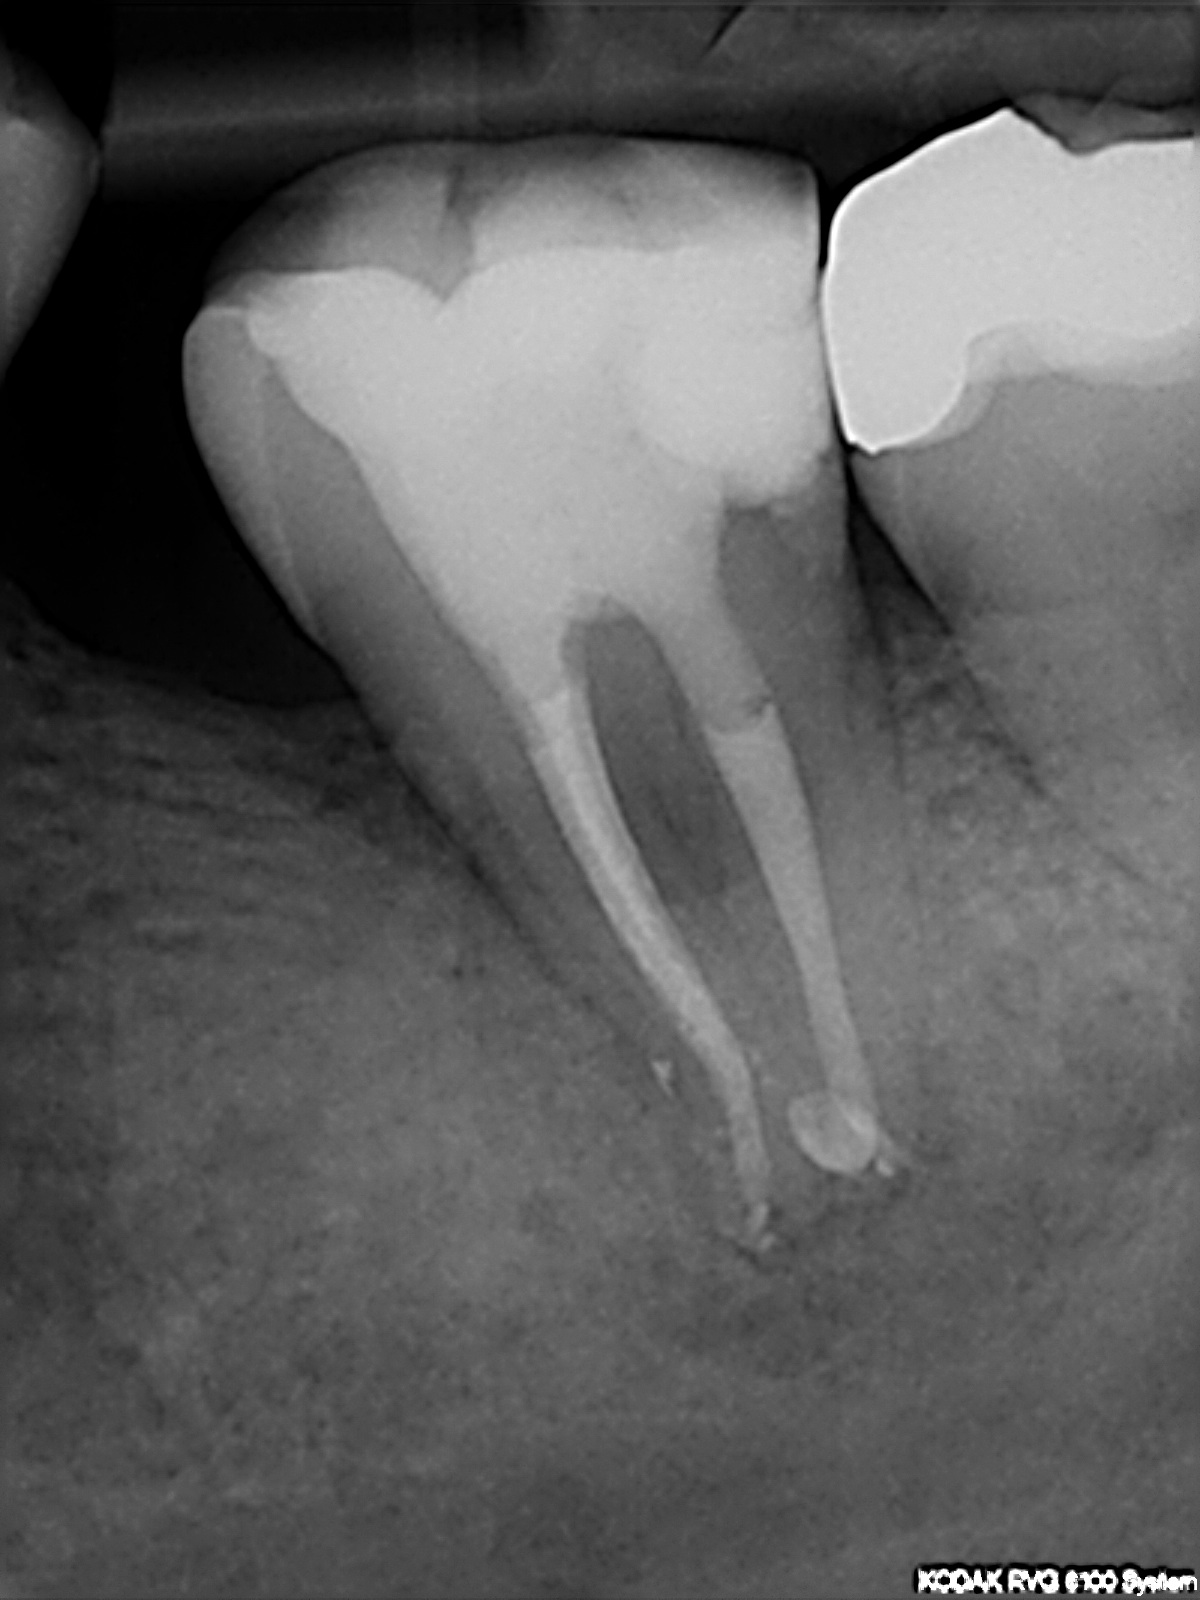

Interessante Kanalanatomie – Recall (4)